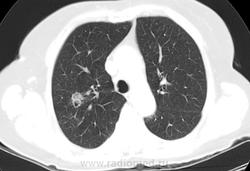

80 лет. Приехала к дочери из другого города. Последняя флюорография в 2010 г., на контроль не вызывали. Появился кашель. После флюорографии ( имеется плохой бумажный носитель) выполнили КТ ОГК. Со слов больной, в 1948 г. находилась в туберкулезном санатории. Подробностей не помнит. Специалисты по КТ заподозрили туберкулёму, каверну. Уж, больно тень нехорошая. Решил с Вами обсудить. Есть ли данные за рак? И каверна ли это? Рисунки представляю. Жизнь неумолимо диктует освоение КТ! Жду. С уважением Nik.

Впечатление туберкуломы с раком. Лимфангит (-оит, -иит), матовость нежная перифокально, очень может быть, что и очаговость.

Во-первых, такое впечатление, что образование состоит из нескольких узелков. От него идут в стороны линейные тени, скорее всего лимфангит, вокруг признак матового стекла. Распад есть, но существует ещё и полостная форма рака. Плюс возраст. Я за рак.

В S3 справа определяется участок уплотнения с четкими ровными контурами и уплотнением в центре (вероятнее всего туберкулема ).на границе S3 и S2определяется участок с разной денситометрческой плотностью,вероятнее всего сформированный из нескольких узлов(мультицентричный рост) имеющие вытянутую  ,округлую форму с бугристыми контурами ,с содержанием в структуре мелких бронхов,которое в  периферических отделах окруженно уплотнением по типу матового стекла(лимфостаз или перифокальное воспаление ),распорстраняющийся до костальной плевры,в ниже лежащем узле определяется участок распада с довольно плотной  капсулой ,в одном из сканов прослеживается бронх проникающий в образование ,выше и ниже участка определяются выраженные интерстициальные изменения. в средостенном окне, 2 скан-определяется участок деструкции ребра по ее  задней поверхности ,смешанного типа ,в участке прилежащем к мышцам определяется размытость контура с местами нарушением целостности замыкательной пластинки(исключить метастаз!!)у меня 3 диагноза :1)бар(локальная форма),2)карцинома и 3)множественные туберкулемы.в первую очередь исключить первые два,выяснить природу изменений в ребре

Больше в пользу рака. Неровные  лобулярные контуры, разная плотность (есть участки употнения по типу матового стекла. ззлокачественный характер кальцификации - эксцентрично, неравномерно, точечно). В образовании есть нарушение легочной архитектонники в виде расширениея мелких бронхов.  Вообщим, мне кажется (на 95% уверен) - это  периферический рак (ну или БАР)

Air Bronchogram sign Recent studies have showed that an air bronchogram is more commonly seen in malignant pulmonary nodules. It is most commonly seen in BAC (bronchoalveolar cell carcinoma) and adenocarcinoma. The case on the left shows an airbronchogram seen as a linear lucency (broad arrow) and as a more cystic lucency (small arrow) due to the fact that the bronchus is seen en face.

Solid and Ground-glass components Another result from screening studies is that nodules containing a ground-glass component are more likely to be malignant (5). Partly solid lesions with ground-glass components had a malignancy rate of 63%. Nonsolid - only ground-glass lesions had a malignancy rate of 18%. Only solid lesions had a malignancy rate of only 7%.

Кстати на картинке озаглавленной "1. мозговой штурм" выше - есть очеь очень некрасиввый очаг в 6-ке слева (по типу матового стекла), расположенный периваскулярно. Очень подозрительный на мтс.